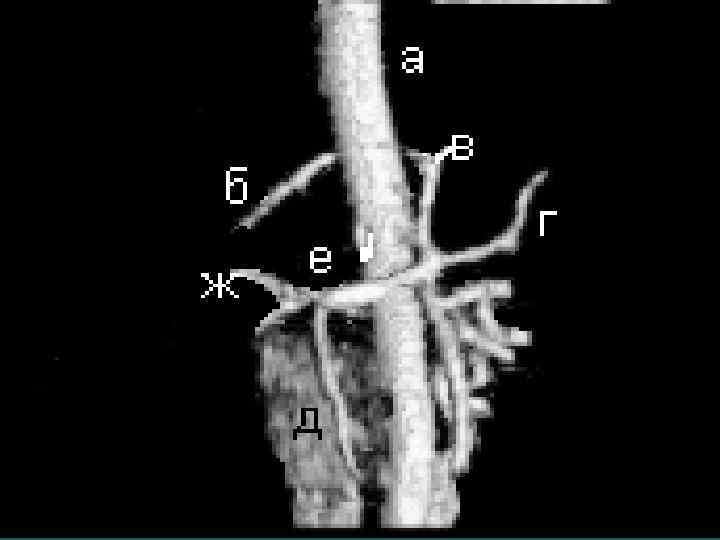

М. Ш. Израилашвили (1990) Регионарные лимфоузлы – гепатодуоденальной связки и задние панкреатодуоденальные. Кроме того лимфооток из печени происходит в лимфоузлы: 1. Вдоль абдоминальной части НПВ (96, 5%) 2. Диафрагмальные (64, 7%) 3. Кардиальные (48, 6%) 4. Левые желудочные (38, 1%) 5. Чревные (12, 4%)